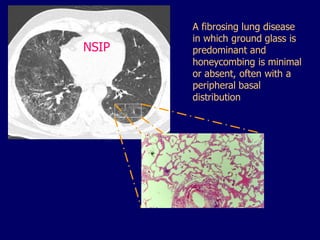

NSIP

A fibrosing lung disease

in which ground glass is

predominant and

honeycombing is minimal

or absent, often with a

peripheral basal

distribution

NSIP A fibrosing lungdisease in which ground glass is predominant and honeycombing is minimal or absent, often with a peripheral basal distribution